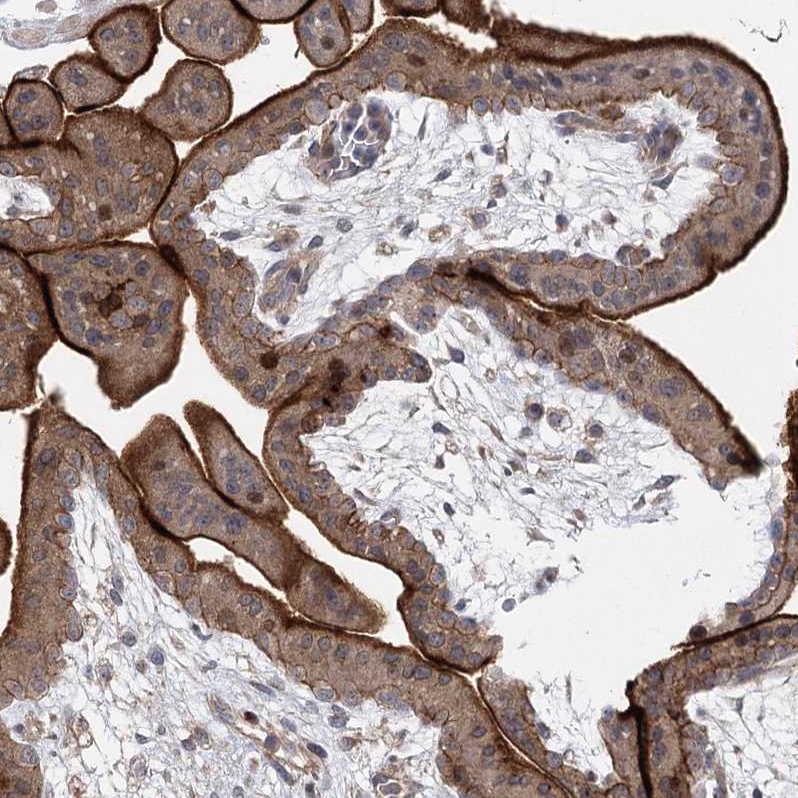

Immunohistochemical staining of human duodenum shows strong membranous positivity in glandular cells.